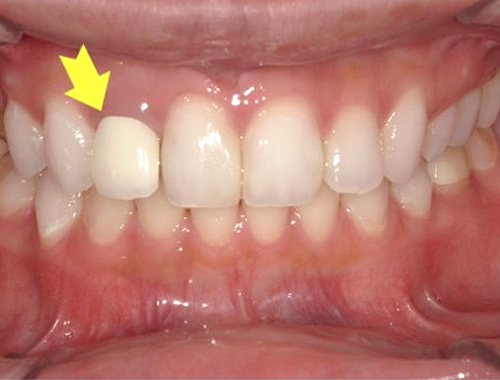

保険診療で使用されていた金属の詰め物(いわゆる銀歯)を、白くて自然な見た目のセラミック(ジルコニア)に変更した症例です。金属の詰め物は強度に優れている一方、笑ったときや口を開けたときに目立ちやすく、長い年月が経つと金属成分が溶け出して歯ぐきが黒ずんで見えることがあります。

それに対し、セラミックの詰め物は見た目がとても自然で、天然歯とほとんど見分けがつかない仕上がりが可能です。金属を一切使用しないため、金属アレルギーの心配がなく、身体にも優しい素材です。

今回使用したジルコニアは、セラミックの中でも特に強度に優れており、歯を薄く削って作製できるという利点があります。一方で、オールセラミックに比べると透明感はやや出にくい素材です。患者さまから「なるべく歯を削らず、強度も確保したい」とのご要望があったため、このジルコニア素材を選択しました。精密に作製されるため適合性にも優れており、しっかりとフィットして虫歯の再発を防ぐ効果も期待できます。

写真では、治療前後の違いをご覧いただけます。黄色い矢印の部分が、実際にセラミックに置き換えた箇所です。治療後は口元の印象が明るくなり、患者さまにも大変ご満足いただけました。

治療期間通院3回(むし歯治療、型取り、セット)、約2週間程度

費用目安税込77,000円×2